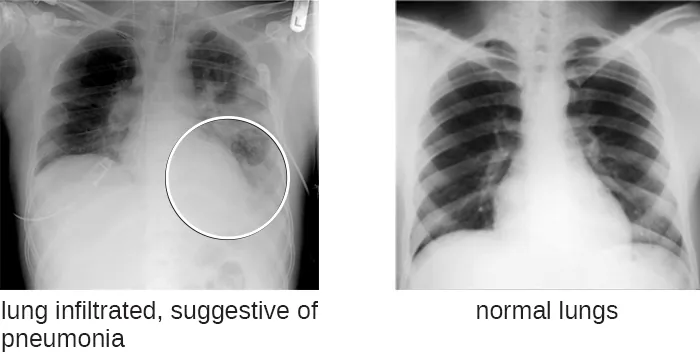

During her physical examination, the PA notes that Barbara’s heart rate is slightly elevated. Using a pulse oximeter, a small device that clips on her finger, he finds that Barbara has hypoxemia—a lower-than-normal level of oxygen in the blood. Using a stethoscope, the PA listens for abnormal sounds made by Barbara’s heart, lungs, and digestive system. As Barbara breathes, the PA hears a crackling sound and notes a slight shortness of breath. He collects a sputum sample, noting the greenish color of the mucus, and orders a chest radiograph, which shows a “shadow” in the left lung. All of these signs are suggestive of pneumonia, a condition in which the lungs fill with mucus (Figure 3.10).

Chest X-rays show ribs and other bones as white and the lungs as black. The left image has significant white cloudiness in the lungs. This lung infiltrate is suggestive of pneumonia. Normal lungs show a smooth, even black color throughout the lungs.

Figure 3.10 This is a chest radiograph typical of pneumonia. Because X-ray images are negative images, a “shadow” is seen as a white area within the lung that should otherwise be black. In this case, the left lung shows a shadow as a result of pockets in the lung that have become filled with fluid. (credit left: modification of work by “Christaras A”/Wikimedia Commons)